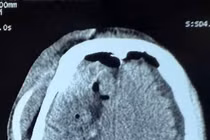

Ngã sau cơn động kinh, người đàn ông 55 tuổi xuất huyết não trán, thái dương